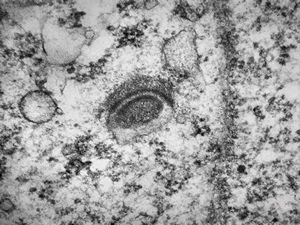

F,50y. | progressive multifocal leukoencephalopathy- viral particles in a glial cell

F,50y. | progressive multifocal leukoencephalopathy- viral particles in a glial cell

F,50y. | progressive multifocal leukoencephalopathy- viral particles in a glial cell